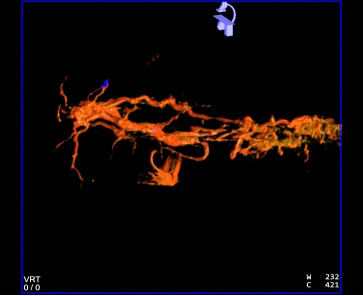

患者仰卧,右侧腹股沟区消毒铺巾,穿刺右股动脉,置入5.0Fr 导管鞘,经鞘进入 RH 导 管,在主动脉弓处成形,选择性进入腹腔干,行血管造影,肝右叶无明显肿瘤染色,肝左动 脉由胃左动脉发出,采用科睿驰医疗提供“智鹏”2.0Fr 微导管选择进入肝左动脉造影,行CBCT 扫描可见肝左内叶肿瘤强化病灶,大小约 1cm,肝左外叶病灶与胃左动脉分支共干,无法避开进一步超选择,超选择进入肝左内叶,造影明确到达把血管,选用 100-300μm“睿 渊”DiaSphere®载药微球加载 50mg 表柔比星,载药完毕后,予注入 2ml 载药微球,再 次行 CBCT 扫描,原肝左内叶病灶无强化,术中患者生命体征平稳,撤出导管,压迫止血、 包扎,患者安返病房。

术中 CBCT 可见肝左内叶肿瘤强化病灶

CBCT 扫描血管重建可见,血管迂曲及靶病灶大小和位置

栓塞结束后 CBCT 扫描,原肝左内叶病灶无强化